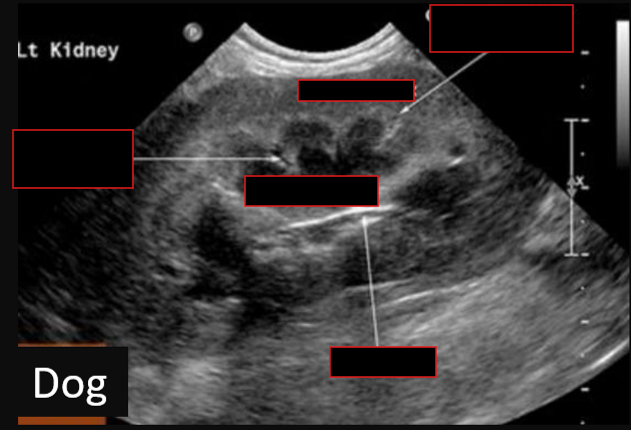

9

Label this frontal/dorsal view kidney ultrasound